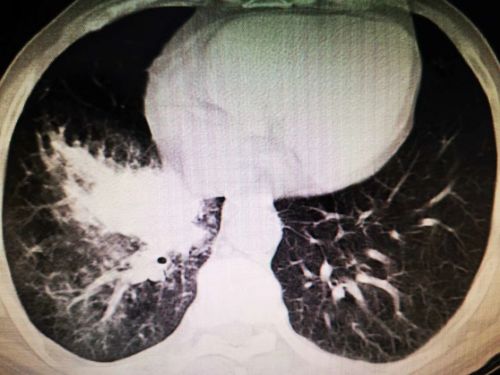

6月上旬,湖南宁乡75岁的姜爷爷连续4天发高烧,最高体温达到40.1℃,可自行退烧,除阵发性腹痛外没有其他不适。无规律的高热让平时身体硬朗的老人没了精气神,吃了几天中药不见好转,在家人的反复劝说下,来到捷克论坛 就诊。初步筛查排除新冠肺炎后,老年医学中心何翠娥副主任医师仔细询问病史,并为其进行详细的体格检查, CT 检查提示:1.右下肺阻塞性肺炎;2.右下肺团块灶,性质待定,考虑肿瘤可能性大。随即将其收入老年医学中心二病室,做进一步的检查和治疗。